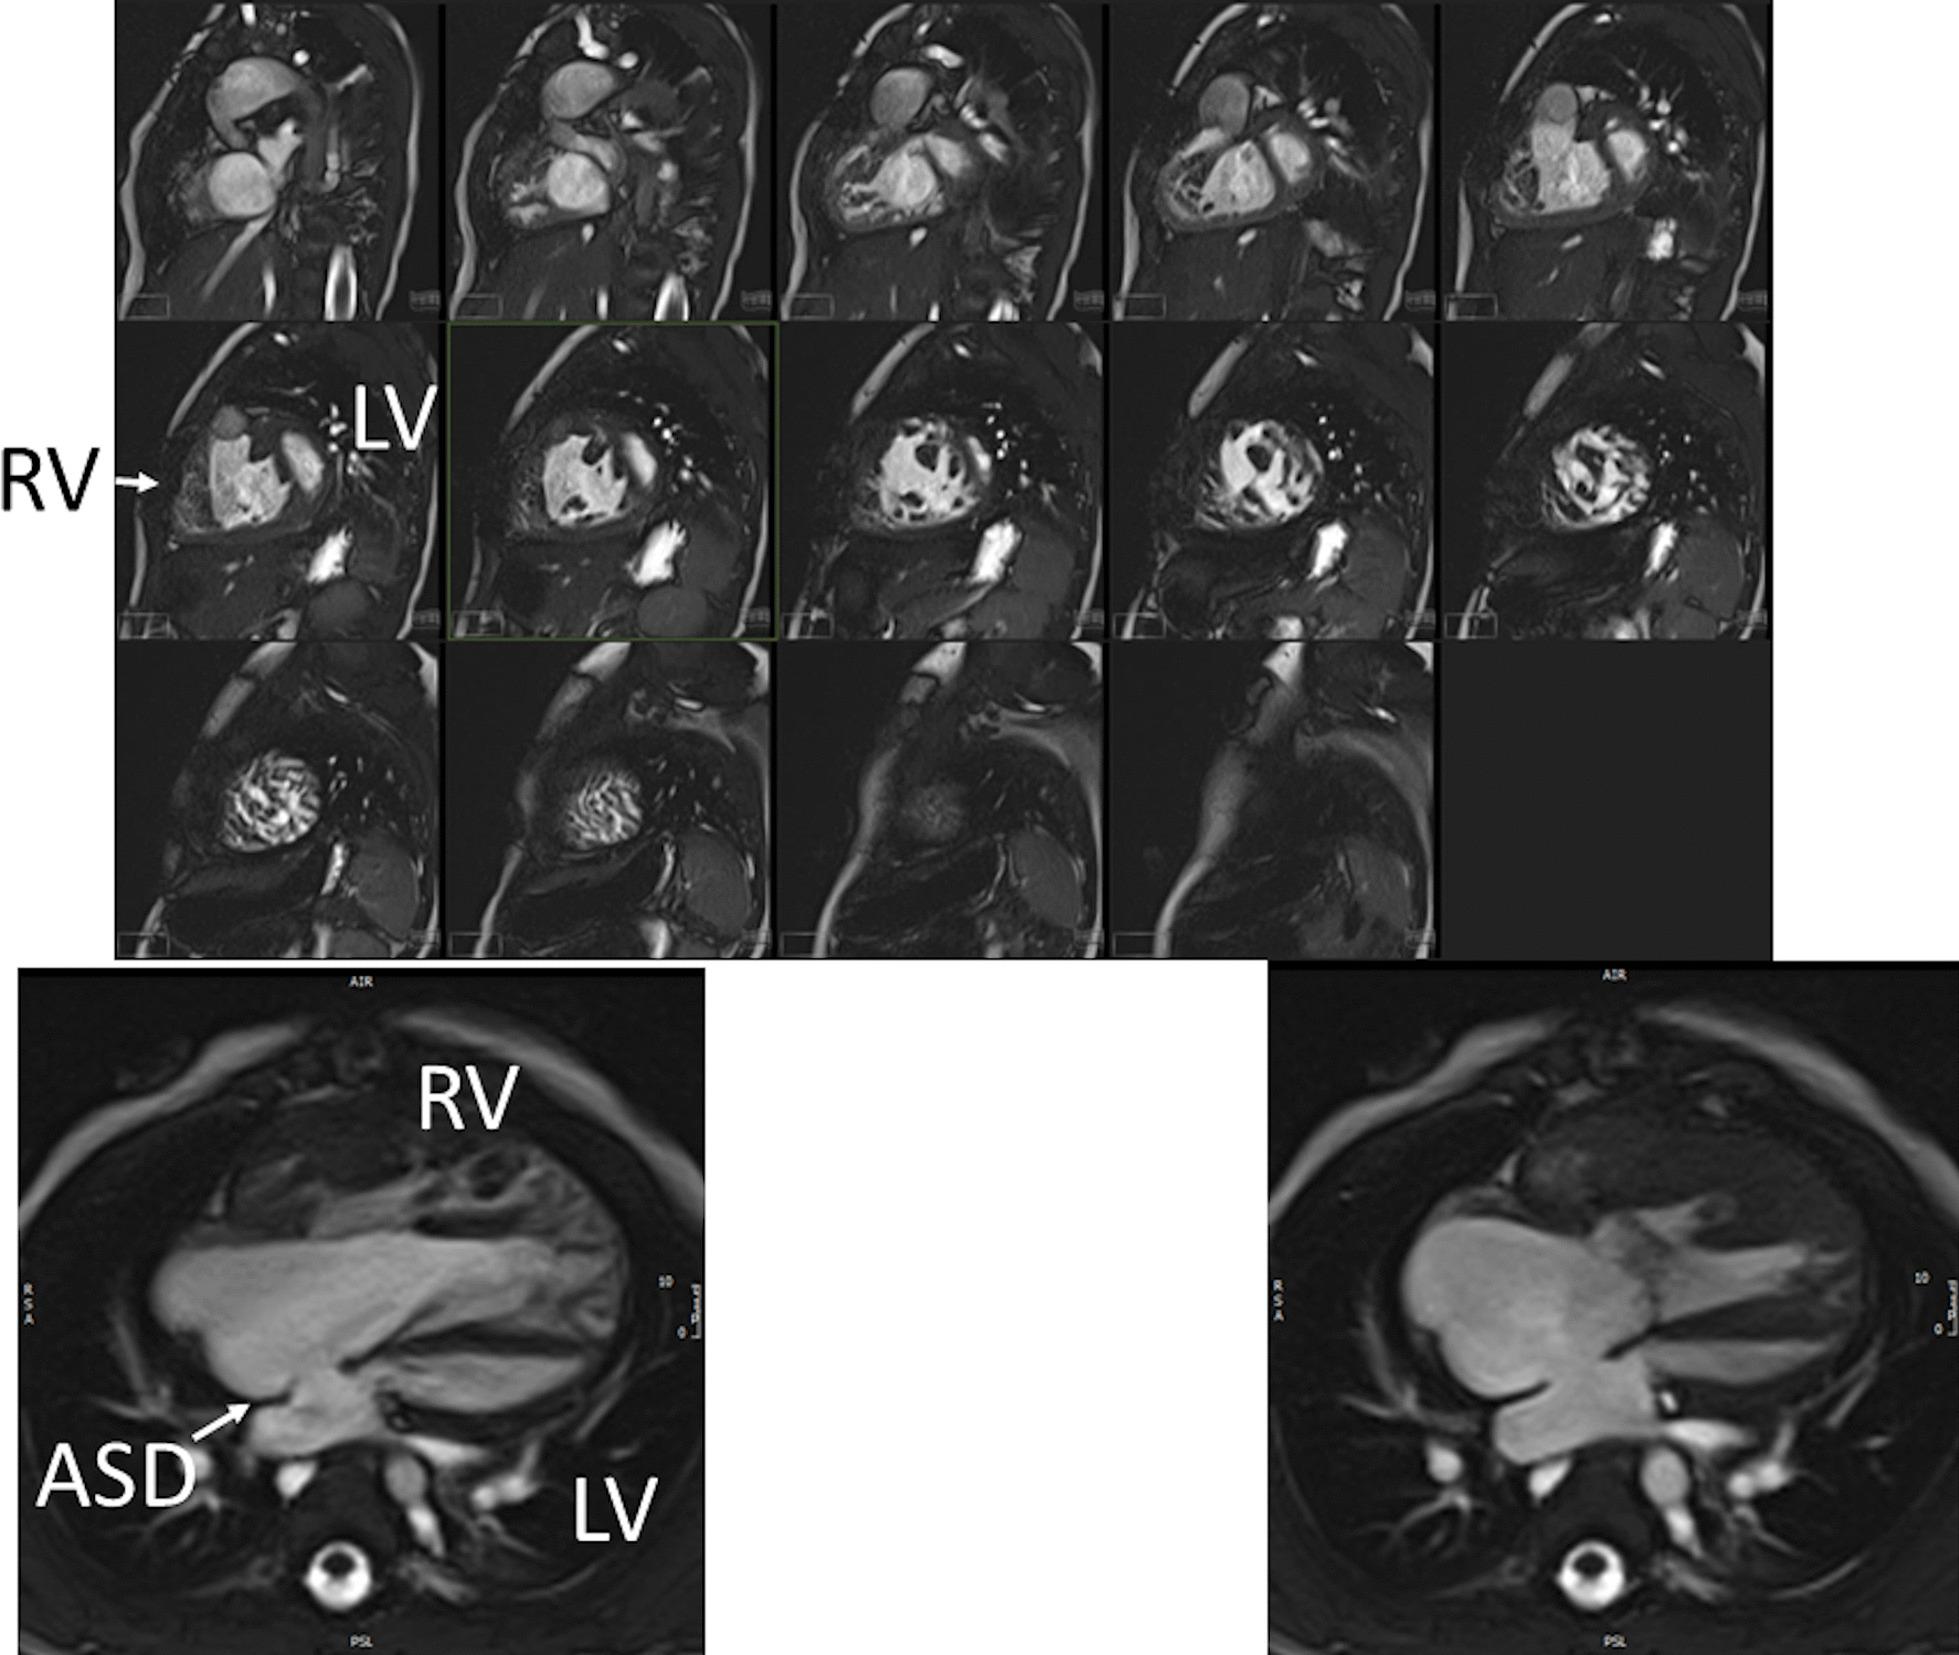

Cardiovascular magnetic resonance (CMR) has been utilized in the management and care of pediatric patients for nearly 40 years. It has evolved to become an invaluable tool in the assessment of the littlest of hearts for diagnosis, pre-interventional management and follow-up care. Although mentioned in a number of consensus and guidelines documents, an up-to-date, large, stand-alone guidance work for the use of CMR in pediatric congenital 36 and acquired 35 heart disease endorsed by numerous Societies involved in the care of these children is lacking. This guidelines document outlines the use of CMR in this patient population for a significant number of heart lesions in this age group and although admittedly, is not an exhaustive treatment, it does deal with an expansive list of many common clinical issues encountered in daily practice.

心血管磁共振(CMR)在儿科患者的管理和护理中已经应用了近 40 年。它已经发展成为评估最小的心脏的宝贵工具,用于诊断、介入前管理和随访。尽管在许多共识和指南文件中提到,但在儿科先天性心脏病和后天性心脏病领域,目前还缺乏一份由众多参与儿童护理的学会共同认可的、最新的、独立的、针对 CMR 使用的大型指南。本指南文件概述了 CMR 在该年龄段的许多心脏病变中的应用,尽管不能说是详尽的治疗方法,但它确实涉及了在日常实践中经常遇到的许多常见临床问题的广泛列表。